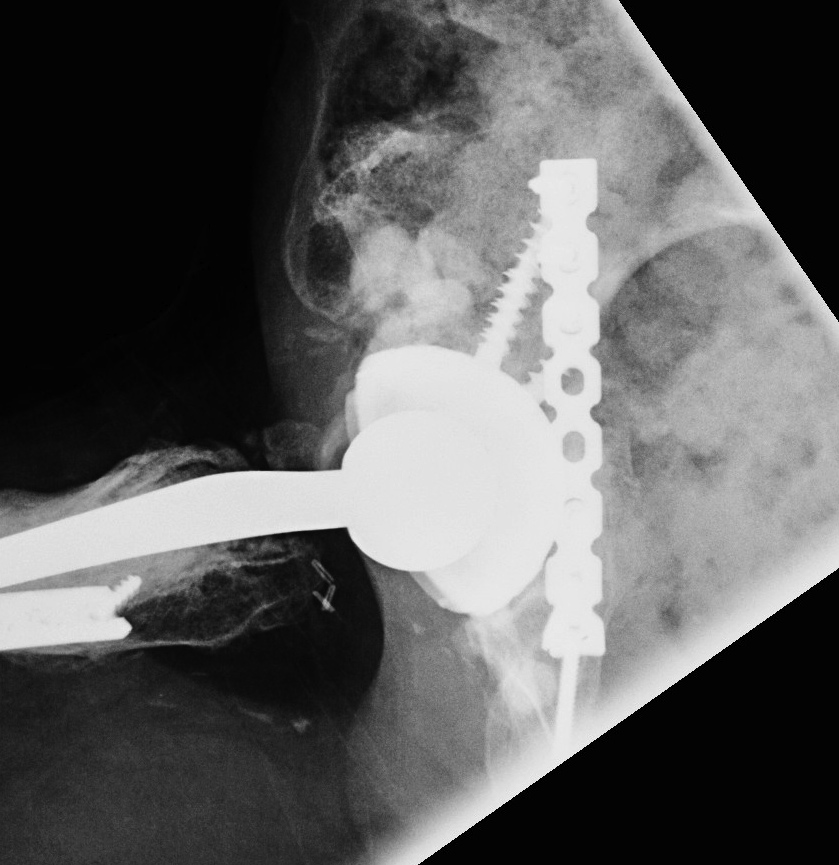

1. Structural Allograft + Cage

Indications

- when inadequate bone stock precludes the use of uncemented acetabular components

Theory

- cannot implant onto allograft

- graft under the cage

- secure with cage

- cement poly into it

Technique

- allograft reconstruction of rim with femoral head

- allograft particulate material in base

- secure cage to posterior column ilium and ischium

- 3 screws in each

- cement all poly cup into cage

Results

- 75% 10 – 15 year survival